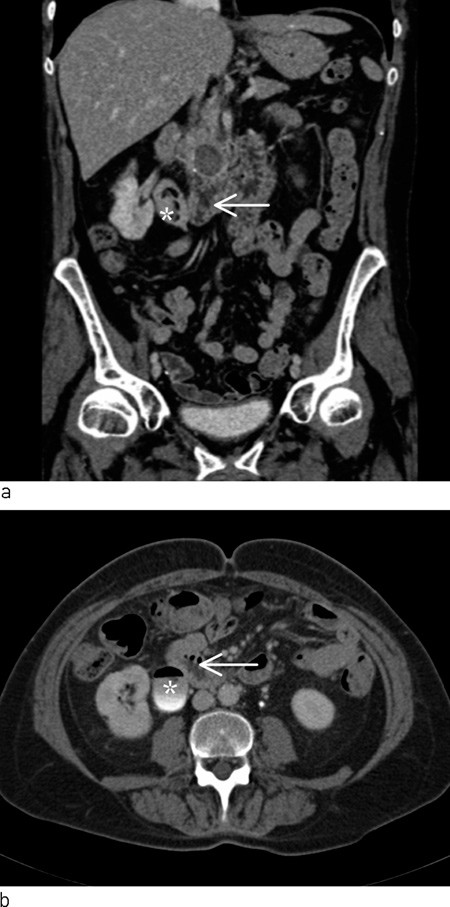

The patient was examined at the Urology Clinic three weeks later. Exploratory blood tests showed haemoglobin 13.0 g/dl (11.7 – 15.3 g/dl), CRP 3 mg/l (< 10 mg/l), carbamide 9.0 mmol/l (3.0 – 6.5 mmol/l), creatinine 81 μmol/l (50 – 90 μmol/l). Glucose was not tested. Cystoscopy revealed abundant cloudy urine in the urinary bladder. No concrements or other foreign bodies were detected, and no pathology in the mucous membrane of the bladder. Urine cytology showed normal cells without atypical features. A urinary tract CT was ordered to investigate whether the patient’s haematuria might be due to concrements or processes in the upper urinary tract or in relation to the urinary tract. Two weeks later, a CT scan of the kidneys and urinary tract was performed without and with contrast medium in two phases. These revealed abundant gas in the urinary bladder and in the right collecting duct system. The patient had a pronounced renal pelvis with some filling defects on the right. The calyces and ureter were slender. The duodenum was close to the pronounced renal pelvis. The left kidney and ureter were normal. Calcifications and a cyst 1.5 cm in diameter were detected in the head of pancreas (Fig. 1).

Figure 1  CT urinary tract with intravenous contrast in secretion phase. Coronal (a) and axial (b) reconstruction show close…

Figure 1 CT urinary tract with intravenous contrast in secretion phase. Coronal (a) and axial (b) reconstruction show close relations between duodenum (arrow) and pronounced renal pelvis with gas and filling defects on right side (star). On the coronal reconstruction, cystic filling is also seen in the pancreas cranially of the duodenum